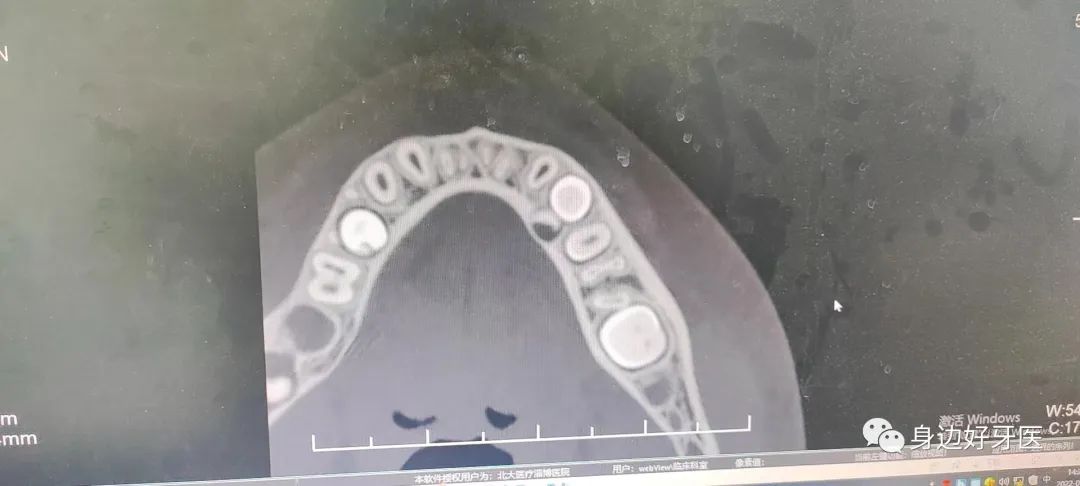

▲口腔全景片可見:除左上區(qū)域有直徑10㎜的牙瘤外,左下方前磨牙區(qū)也存在較小范圍的牙瘤。

近日,細(xì)心的李女士(化名)覺得孩子妞妞(化名)乳牙長時(shí)間滯留、恒牙長時(shí)間未萌出,于是帶其到北大醫(yī)療淄博醫(yī)院口腔科就診??谇豢浦魅蚊两釉\了妞妞,在進(jìn)行全景片檢查時(shí),毛主任發(fā)現(xiàn)其左側(cè)上頜骨中,竟然有一個(gè)巨大的球狀“白影”,有多枚沒發(fā)育完全的牙齒,像巖石一樣阻礙了新生門牙的生長,這些沒有發(fā)育完全的牙齒,正是導(dǎo)致妞妞她沒有萌出恒牙的“罪魁禍?zhǔn)?,而這正是“牙瘤“?!把懒觥毙枰中g(shù)切除,才能恢復(fù)牙齒健康,讓正常的牙齒健康生長,毛主任耐心對(duì)李女士講解后,李女士迫切希望盡快手術(shù)治療。?

毛亮主任與口腔科專家為其制定了詳細(xì)手術(shù)方案,在手術(shù)室醫(yī)護(hù)人員的密切的配合下,毛主任利用無痛麻醉技術(shù)進(jìn)行精準(zhǔn)麻醉,拔除對(duì)應(yīng)部位乳牙,去除牙瘤表面的骨質(zhì),打開一個(gè)微小開口,取出了左上區(qū)直徑約1.1厘米及左下區(qū)直徑約0.6厘米的“牙瘤”,手術(shù)僅耗時(shí)30余分鐘。經(jīng)毛主任清點(diǎn),牙瘤中竟有約30多顆大小不同、形狀各異阻礙新生牙齒生長的小牙齒。